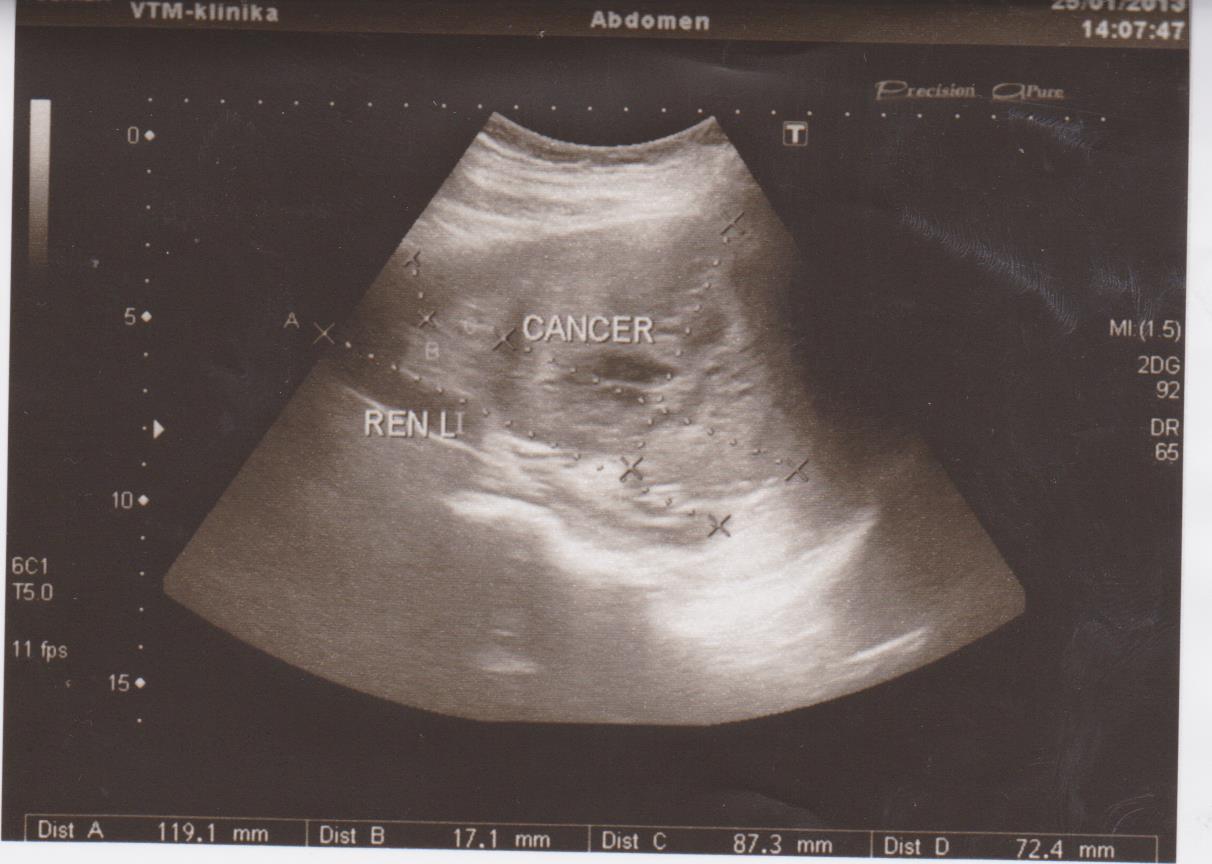

Частые болезни: кисты, новообразования (ангиомиолипомы, гемангиомы, фибромы…), конкременты (камни), расширение мочевых путей (расширение лоханки или чашечек — пиелоэктазия, гидронефроз), хроническое воспаление (пиелонефрит), смещение почек (опущение — нефроптоз, нахождение в нетипичном месте — дистопии), удвоение почки, рак почки…

Ниже я привел пару УЗИ снимков из практики, все они есть в галерее УЗИ на сайте, смотрите и не пугайтесь: